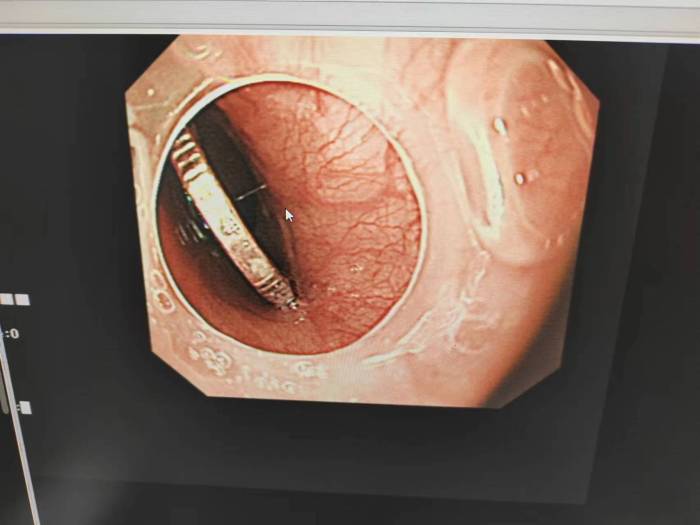

杨先辉通过内镜观察,见有一枚1角硬币嵌顿在食道两壁,经过反复调整角度,异物钳紧夹在硬币中间,边充气边缓慢退镜,防止划伤胃及食管粘膜。最后,在胃肠镜室、麻醉师和护士的相互配合下,成功取出硬币,使患儿转危为安。